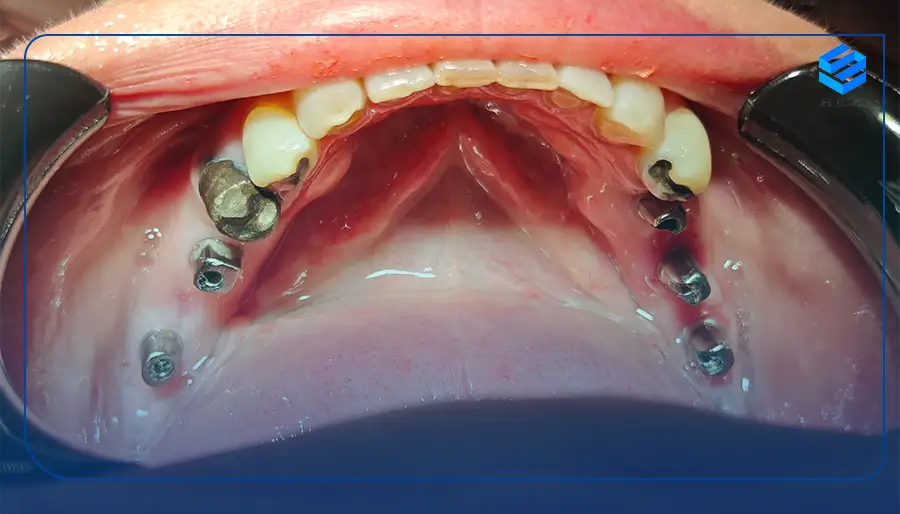

در ایمپلنت دندان متحرک یا کاشت دندان متحرک به جای اینکه روی لثه قرار بگیرند روی ایمپلنتهای دندانی قرار میگیرد و به راحتی امکان درآوردن و گذاشتن آن وجود دارد. این نوع ایمپلنتها مزایای بسیاری دارند و از تحلیل استخوان فک جلوگیری میکنند ضمن اینکه ظاهری طبیعی و زیبا میبخشند.